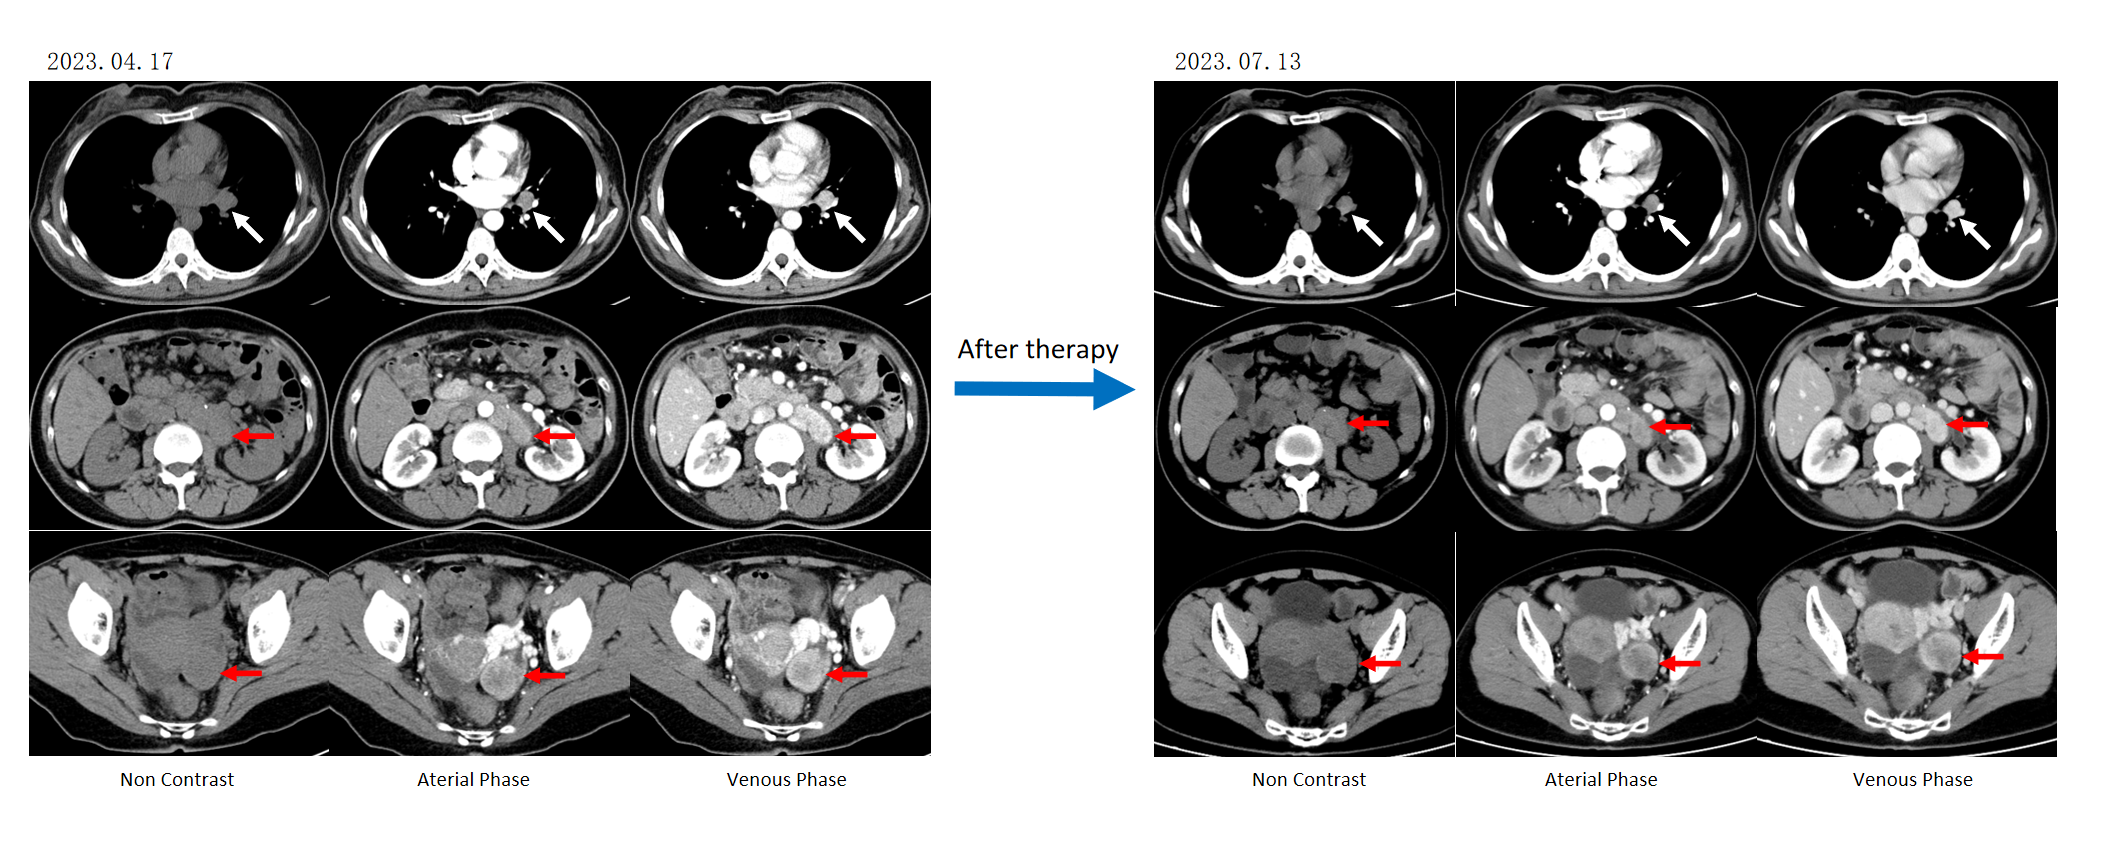

患者于2018-11接受胰体尾切除术+脾切除术+肝部分切除术+微波消融术。68 Ga PET/CT提示:神经内分泌肿瘤累及双肺门、纵膈、膈脚后、腹膜后淋巴结;肝脏多发累及;左肾上腺累及。术后病理提示患者SSTR-2阳性,因此自2018年12月至2019年8月,患者接受奥曲肽长效微球(30mg im q4w)治疗。2019-3-5 CT增强示:肝转移瘤治疗后未见明显活性,胰腺术区未见肿瘤复发,右膈角淋巴结转移瘤稳定。2019-8-15 68 Ga PET/CT提示:左锁骨新增病灶;双肺门、纵膈、膈脚后、腹膜后淋巴结、肝脏多发、左肾上腺较前进展。

2019年,患者出现疾病进展后,调整治疗方案为奥曲肽(30 mg,q4w)联合CAPTEM方案(卡培他滨+替莫唑胺,q4w)进行姑息化疗。2019年11月1日复查68Ga PET/CT显示,病灶较前明显缩小。2020年3月CT复查显示疾病稳定(SD)。联合奥曲肽和CAPTEM方案治疗持续约1年,至2020年9月患者自行中断治疗,未继续接受奥曲肽维持治疗,也未进行规律复诊。2022年1月,因腹胀及乏力症状加重,患者再次就诊。

患者于2022年1月20日开始接受索凡替尼300 mg每日口服治疗,治疗1个月后腹胀症状明显缓解。2022年4月28日CT复查提示转移灶明显缩小。2022年9月,患者再次自行中断治疗。

2023年4月29日,患者开始接受PRRT试验药物177Lu-DOTATATE。2023年7月17日评估疗效为SD。此后,患者每4个月复查一次,疗效均为SD。末次复查时间为2024年3月,仍为SD。但此后患者再次失访。